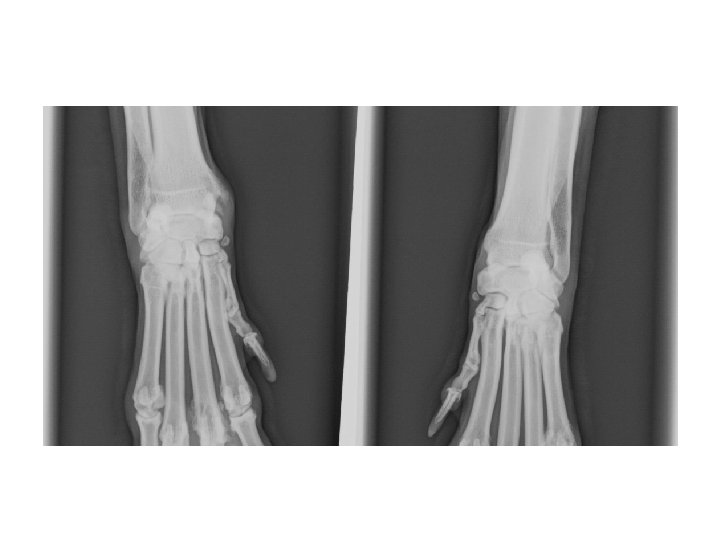

Karpalgelenk